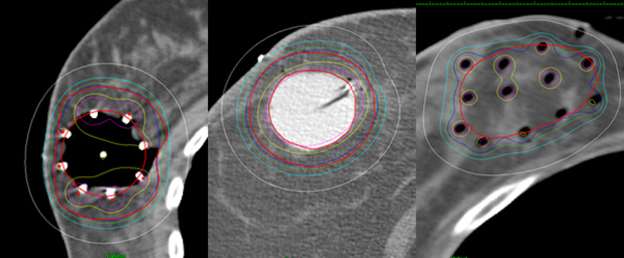

Examples show how the radiation dose (the colored lines, with the white lines representing 50% of the dose) is targeted to the area where the original tumor was using three different partial breast radiation techniques (SAVI, Contura, Tube and Button).

A cartoon depiction of the tube and button implant showing the entrance and exit sites of the hollow tubes.

This is a cartoon example of a SAVI applicator sitting inside of a lumpectomy cavity and showing that a turn-key is used to expand the struts of the applicator so that it fits snug along the edges of the cavity.